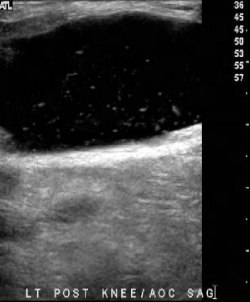

Identify this image.

Baker’s cyst